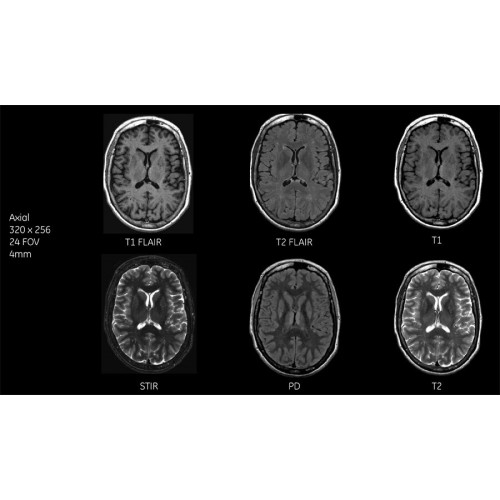

Детализация изображений

Система SIGNA Pioneer воплощает поразительные достижения в области визуализации. Передовая технология Total Digital Imaging (TDI) позволяет добиться большей четкости изображений и на четверть повысить соотношение сигнал/шум.

Благодаря революционному программному пакету Silent Suite уровень шума снижается до 77 дБ, что всего на 3 дБ выше уровня окружающей среды. Программный пакет Silent Suite теперь включает полный пакет приложений для исследования ЦНС (T1, T2 FLAIR, DWI10, МРА). Кроме того, мы расширили возможности визуализации Silent за пределы ЦНС для исследований скелетно-мышечной системы и позвоночника. Silent Suite – платформа, содержащая в себе все импульсные последовательности для бесшумного сканирования.